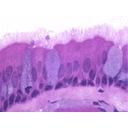

OlfactoryEpith.jpg